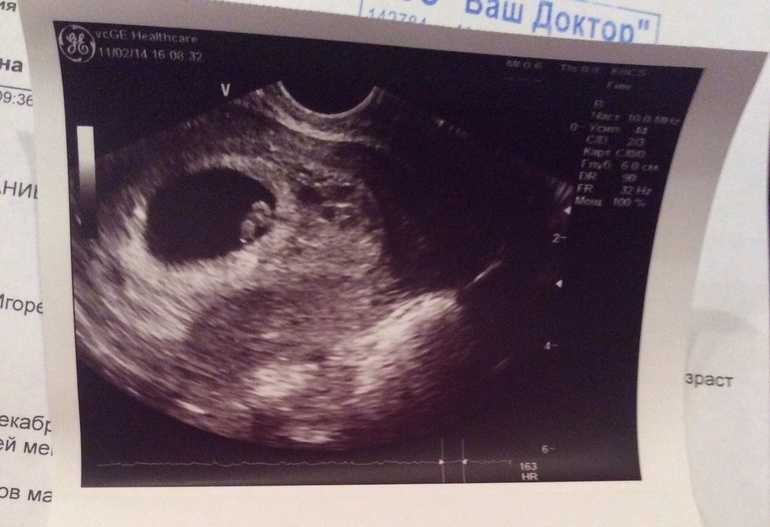

Но как же выглядит 8 мм плодное яйцо на УЗИ? На экране аппарата оно предстает в виде небольшого темного кружочка с четкими границами. Внутри этого кружочка можно различить крошечное светлое пятнышко — это и есть зародыш, который на этом сроке имеет размер всего 1-2 мм. Удивительно, не правда ли? В этой миниатюрной структуре уже начинают формироваться основные органы и системы будущего человека.

Когда будущие родители впервые видят 8 мм плодное яйцо фото на мониторе УЗИ, их часто охватывают смешанные чувства — от восторга до легкого недоумения. «И это наш малыш?» — часто спрашивают они. Да, это действительно так! На фото 8 мм плодное яйцо выглядит как небольшой темный кружок с четкими границами. Внутри него можно различить маленькое светлое пятнышко — это и есть зародыш.

На ранних УЗИ-снимках 8 мм плодное яйцо выглядело как небольшое темное пятно округлой формы. Внутри него едва можно было различить крошечную светлую точку — зародыш. Эти черно-белые фото, хоть и не отличались особой четкостью, все же позволяли врачам оценить размер плодного яйца и наличие эмбриона.

С развитием технологий качество изображения значительно улучшилось. Современные 2D УЗИ дают более четкое представление о структуре плодного яйца. На таких снимках можно различить не только сам эмбрион, но и желточный мешок, амниотическую полость. 8 мм плодное яйцо фото, полученное с помощью современного 2D УЗИ, выглядит как четко очерченный темный круг с небольшим светлым включением внутри.